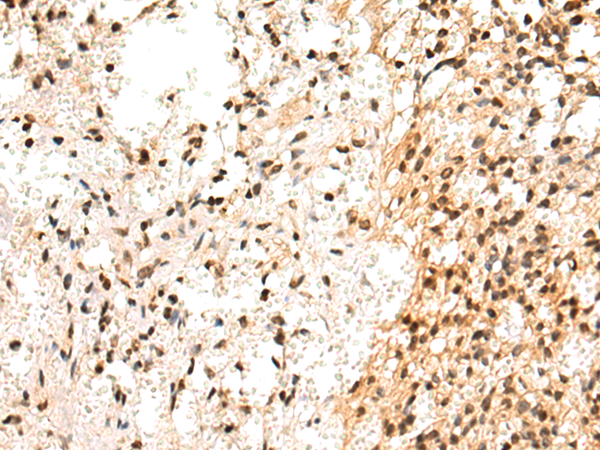

IHC positive control: |

Human breast cancer and Human prostate cancer |

IHC Recommend dilution: |

50-200 |